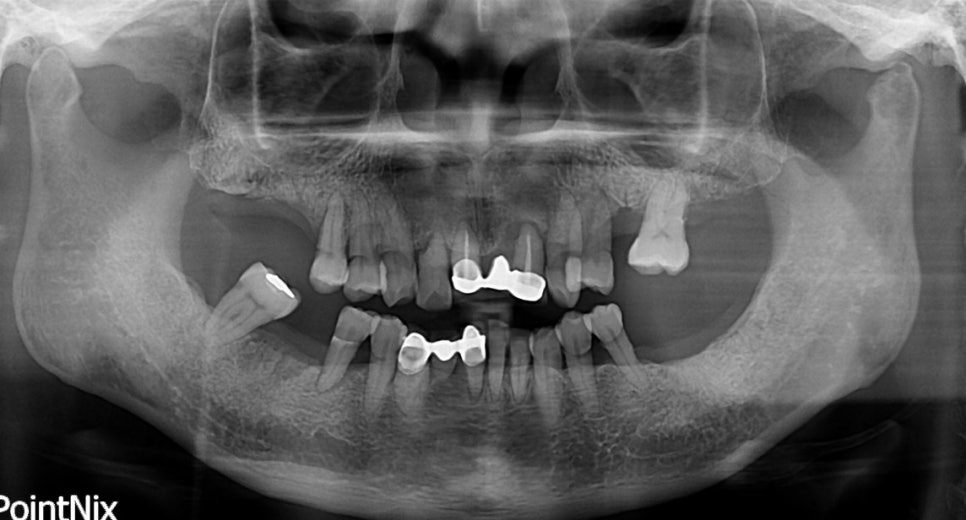

당뇨병 환자로 치주염을 앓고 있을 때의 X-RAY

당뇨질환을 가지고 계신 분 중 치주염을 앓고 계신 경우가 상당히 많습니다. 이러한 원인은 당뇨로 인해 면역기능이 약화되어 세균 감염의 위험이 일반 경우보다 높습니다. 당뇨병의 여러 합병증 중에 잇몸병은 6번째 정도 흔한 합병증이며,

또한 당뇨를 앓고 있는 경우 잇몸병을 치료하지 않고 방치하는 경우, 잇몸 염증이 심해지면서 혈압이 상승되고 염증이 인슐린의 효과를 감소시키는 화학적 변화를 유발시켜 당뇨병을 더욱 악화시킬 수 있습니다.

일반적인 분들도 해당되는 내용이지만 당뇨질환을 앓고 계신 경우, 침과 잇몸 분비액의 포도당 농도가 증가되어 상태가 악화되는 시간이 매우 빠르게 진행됩니다.